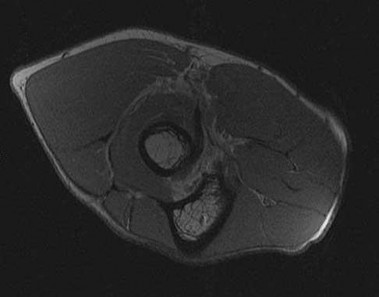

A 22-year-old man sustains an injury to his right knee in a motor vehicle collision. Figure 22a is the posterior stress radiograph of the involved knee, and Figure 22b is a selected MR image that identifies the injured structure.

CLINICAL SITUATION FOR QUESTIONS 22 THROUGH 25

Which relationship is noted for the structure identified by the arrow in Figure 22b? 24

The stress radiographs demonstrate posterior instability of the right knee in flexion. The MR images demonstrate injury to both the anterior and posterior cruciate ligament (PCL), with the stump identified with the arrow on the MR image (Figure 22b). The PCL has 2 functional bands. The anterolateral bundle originates from the roof of the intercondylar notch. It runs in a posterolateral direction onto the tibial crest between the posterior attachment of the medial and lateral menisci. During a double-bundled posterior ligament reconstruction, the

anterolateral bundle is tensioned with the knee in a position of mid flexion. The posteromedial bundle has a variable pattern of tension both in extension and in high flexion. Tensioning of the posteromedial bundle in extension may contribute to resistance against knee hyperextension.

The meniscofemoral ligaments are variably present. Although 93% of knees have been reported to have at least 1 meniscofemoral ligament present, both ligaments are simultaneously present in approximately 50% of knees. The ligament of Humphrey (anterior meniscofemoral ligament) and ligament of Wrisberg (posterior meniscofemoral ligament) are delineated by their anatomic relationship to the posterior cruciate.